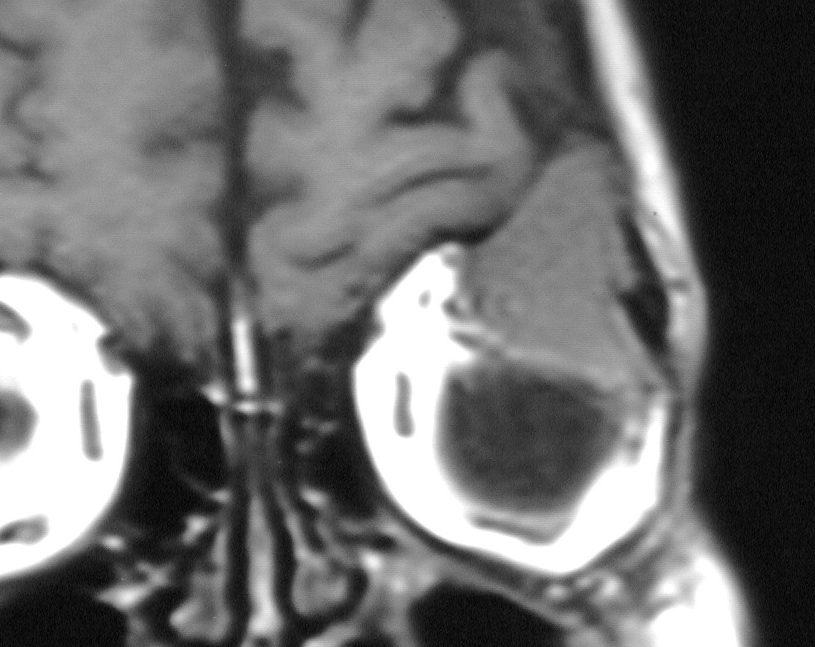

| extramedulläres Plasmozytom | Das MRT zeigt eine koronare Schicht durch die Orbita mit einem extramedullären Plasmozytom![]() | |||